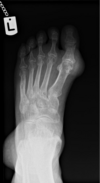

**Gout of MTP** Soft tissue swelling in early disease Periarticular erosions ‘punched out lesions’ in late disease Normal joint space